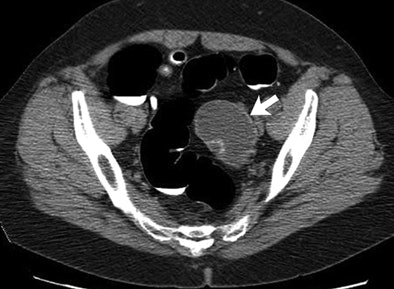

| Adnexal pathologic findings (arrow) identified at routine CTC screening and surgically removed after further workup include mucinous cystadenoma. Image republished with permission of the Radiology Society of North America from Radiology, October 2010, Vol. 257:1, pp. 144-150. |